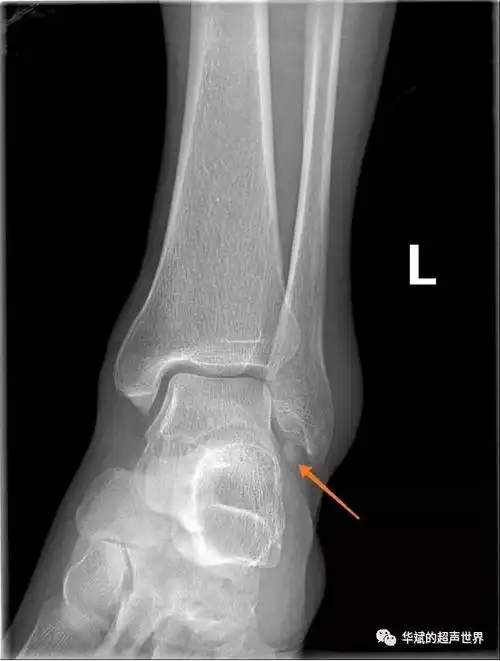

外踝处腓骨内下方箭头所示的的类圆形高密度影,边缘高密度缘完整,腓骨